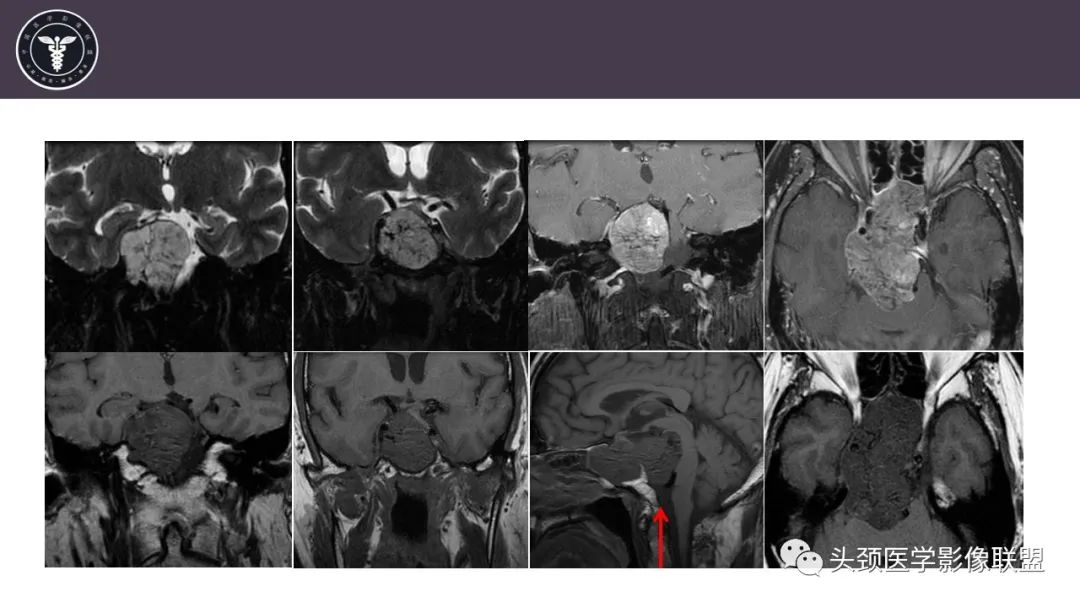

病例1

【病例】斜坡区骨巨细胞瘤 VS 脊索瘤-2